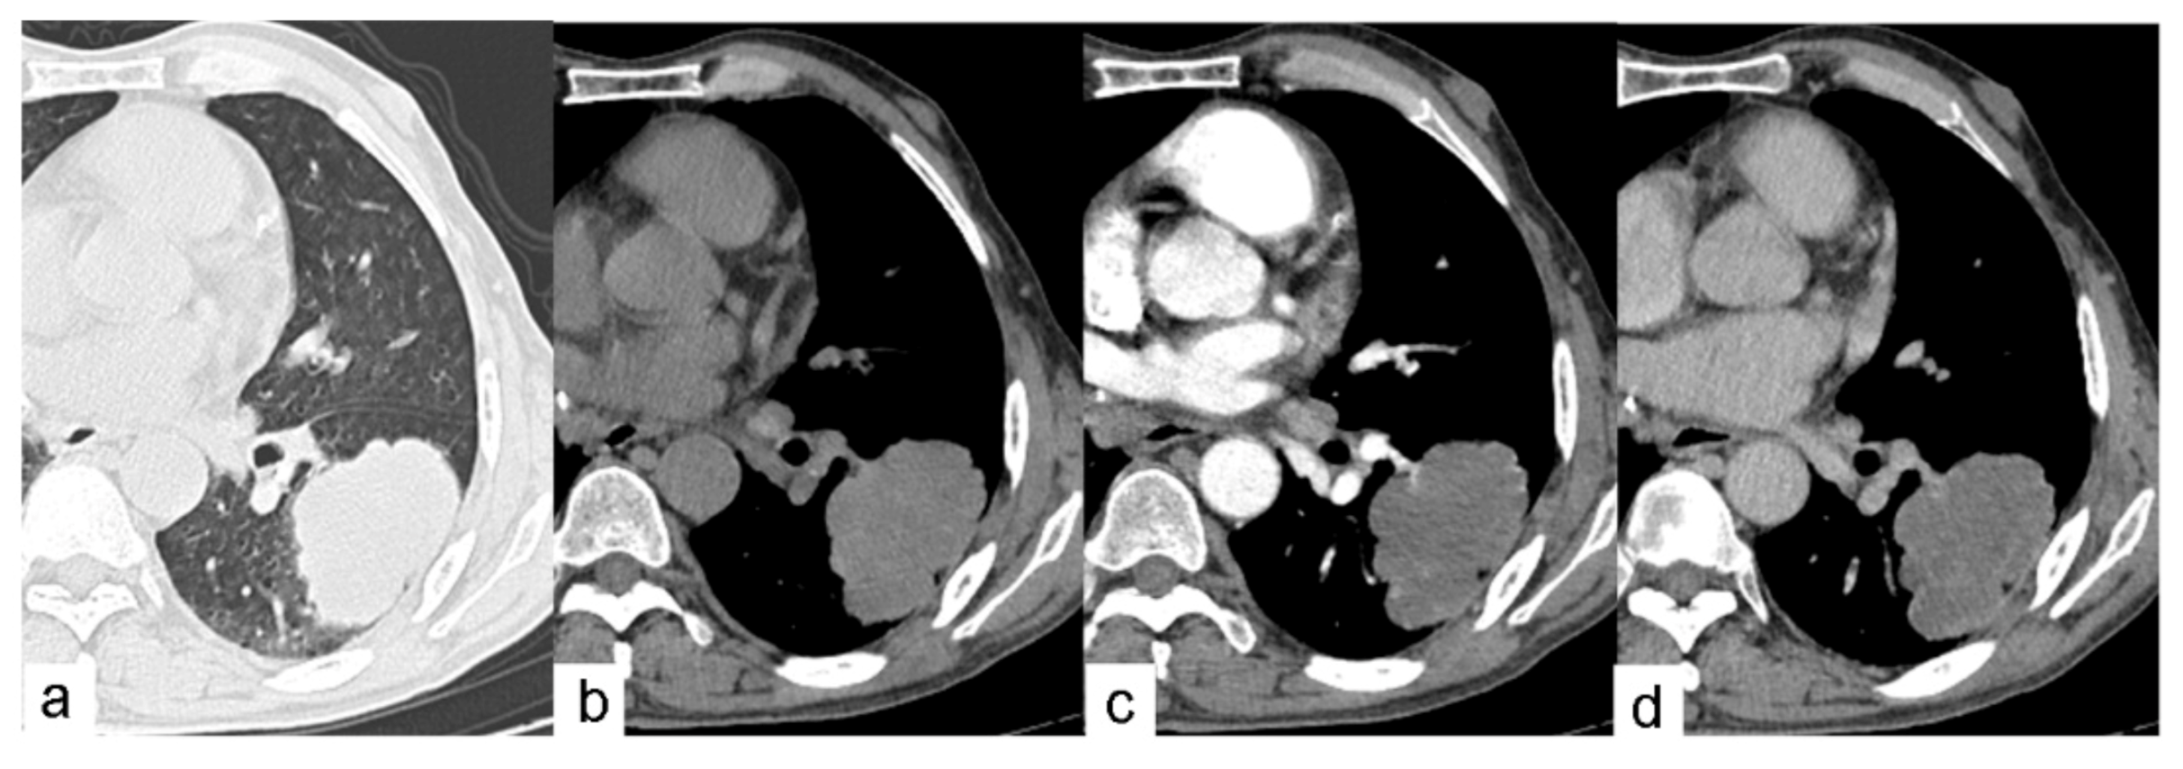

Figure 3. One case of dynamic contrast-enhanced CT scan of the chest in a 62-year-old man. (a) Axial CT image shows a PCE lesion in the left lower lobe of the lung-on-lung window. (b) Axial non-contrast CT image shows the same lesion on the mediastinal window with a CT value of 32HU. This lesion shows no contrast enhancement on (c) arterial phase and (d) venous phase.